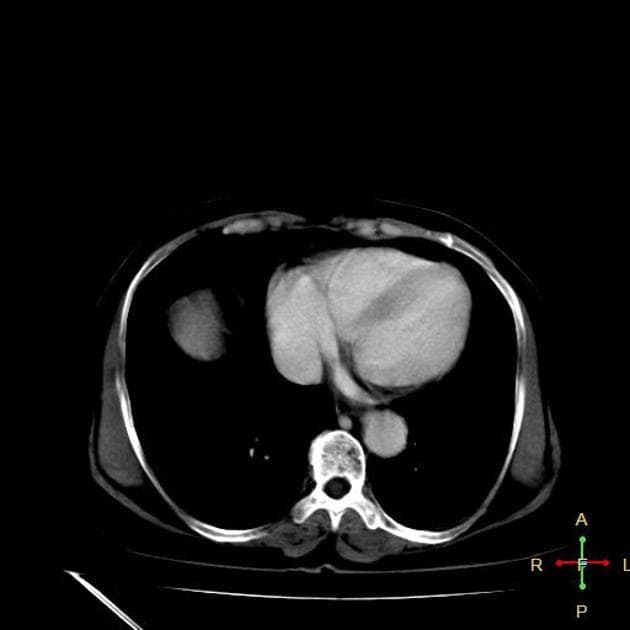

Axial C+ portal venous phase

Ca bệnhÁp xe gan kèm rối loạn tưới máu gan

Áp xe gan kèm rối loạn tưới máu gan

- GAN to (hepatomegaly) kèm gan nhiễm mỡ (fatty liver).

- Thấy một ổ tổ chức dạng nang - nhiều ngăn - giới hạn không rõ (ill-defined multiseptated multiloculated) ở phân thùy VII/VIII của gan, có tăng quang viền (rim enhancement) ngoại vi, kèm theo một ổ vôi hóa và dấu hiệu "cluster sign". Ổ này chèn ép một phần đoạn gan của tĩnh mạch chủ dưới (inferior vena cava - IVC).

- Rải rác ở cả hai thùy gan thấy một số tổn thương giảm tỷ trọng (hypodense lesions) với kích thước khác nhau.

- Thấy nhiều vùng tăng quang tĩnh mạch (venous enhancement) ở cả hai thùy gan, phân bố cả trung tâm và ngoại vi.

- Không xác định được tĩnh mạch gan trái, giữa và phải (left, middle and right hepatic veins).

- Tĩnh mạch cửa (portal vein) thông thoáng (patent).

- Hình ảnh phù hợp với (consistent with) áp xe gan gây chèn ép một phần tĩnh mạch chủ dưới liền kề và rối loạn tưới máu gan (hepatic perfusion disorders).

- Trong trường hợp này, hình ảnh CT cho thấy rối loạn tưới máu gan, có thể thứ phát do không thấy hình ảnh (non-opacification) hoặc tắc (occlusion) tất cả các tĩnh mạch gan do áp xe gan gây ra.

- Tắc các tĩnh mạch gan có thể dẫn đến tăng áp lực xoang gan (sinusoidal pressure), kéo theo tăng lưu lượng động mạch gan, dẫn đến thông động tĩnh mạch cửa chức năng trong gan (functional intrahepatic arterioportal shunt)¹.

Trường hợp này mô tả một áp xe gan mủ ở phân thùy VII/VIII gây hiệu ứng khối, chèn ép một phần đoạn gan của tĩnh mạch chủ dưới và không thấy hình ảnh các tĩnh mạch gan, dẫn đến rối loạn tưới máu gan. Tắc nghẽn dòng chảy tĩnh mạch này làm tăng áp lực xoang gan, từ đó tăng lưu lượng máu động mạch gan, tạo thành thông động tĩnh mạch cửa chức năng trong gan. Hiện tượng này bắt chước các dị dạng mạch máu và cần phân biệt với các bệnh như giãn mạch máu dạng xuất huyết di truyền hoặc hội chứng Budd-Chiari. Đái tháo đường làm tăng nguy cơ áp xe gan, đặc biệt do vi khuẩn gram âm. Dù cấy máu âm tính, chẩn đoán vẫn được xác định dựa trên lâm sàng và hình ảnh. Việc điều trị kháng sinh sớm và theo dõi bằng hình ảnh là rất quan trọng, vì việc bỏ sót theo dõi có thể dẫn đến biến chứng do rối loạn tưới máu kéo dài.